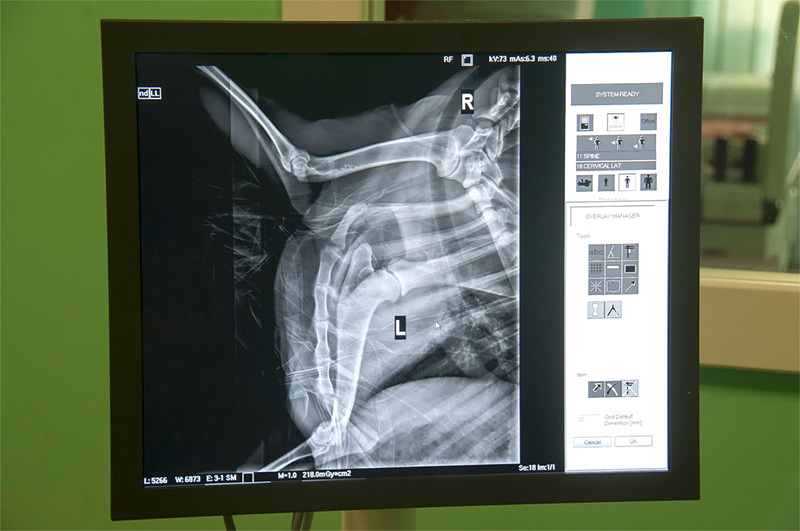

Adobe Veterinary Center provides advanced livestock digital radiology, offering fast, accurate x-rays for diagnosis, treatment, and health certification of ruminants, pigs, and camelids with minimal radiation exposure.

Similar to traditional radiology, digital radiology uses x-ray radiation to produce digital images (x-rays or radiographs) of a patient’s internal structures. Instead of depositing an image on film which then needs to be developed, digital radiographs are developed with the click of a button. We can easily enlarge and enhance these images or share them with veterinary specialists to obtain second opinions.

Veterinarians use digital radiology to assess injuries and evaluate the size, shape, and placement of a patient’s organs, to locate growths and masses, and to assess bone health. X-rays can be used to detect and diagnose a variety of diseases and conditions including musculoskeletal, gastrointestinal, respiratory, and cardiovascular diseases, and more.